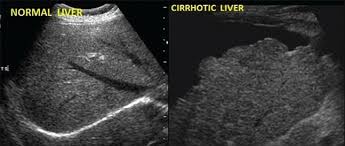

A vizsgáló orvos két fajta eltérést keres, az egyik a szerkezet általános, vagy nagyobb területet érintő elváltozása. Ezek az úgynevezett diffúz szerkezeti eltérések. (3. kép) A másik a körülírtabb eltérések, amelyeket fokálisként is szoktunk hívni (4. és 5. kép).

Diffúz szerkezeti eltérés például a zsírosodás vagy a májcirrózis, fokális szerkezeti eltérés lehet például egy haemangioma, ciszta, vagy daganat.

Májcirrózis

A bal oldali képen normális májat láthatunk, míg a jobb oldali képen egy extrém mértékben cirhotikus májra láthatunk egy példát. Megfigyelhetjük, hogy a máj felszíne kifejezetten egyenetlen felette a sötét (fekete) rész folyadék, ami gyakori velejárója az ilyen előrehaladott májzsugorodásnak.